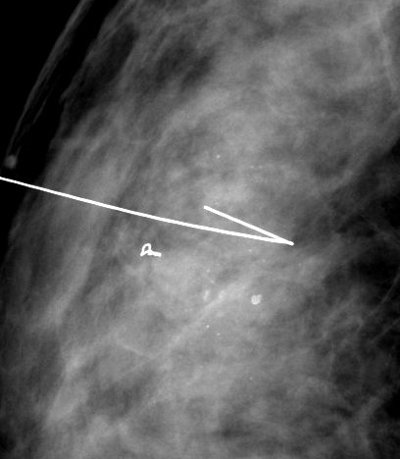

Il s'agit d'une piqûre du sein (de même désagrément qu'une piqûre dans le bras). Quand le radiologue a vérifié par mammographie la position de l'aiguille fine, il enlève l'aiguille, en laissant le repère en place. C'est ce fil que l'on appelle un guide ou harpon .

1 2 3

1 Repérage d'un clip post-biopsies 2 Repérage d'une masse 3 Contrôle per-opératoire de la pièce de tumorectomie (le repère est bien dans la zone d'exérèse)